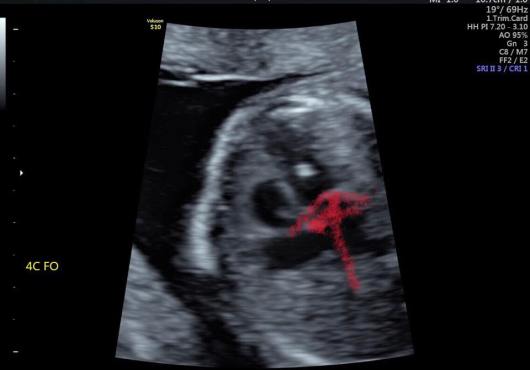

來聊聊心臟小白點吧

正式英文名稱叫做Echogenic intracardiac focus(EIF)